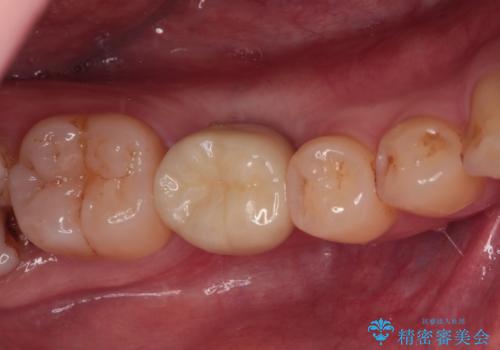

根管治療を行ったままの奥歯 オールセラミッククラウンによる補綴治療